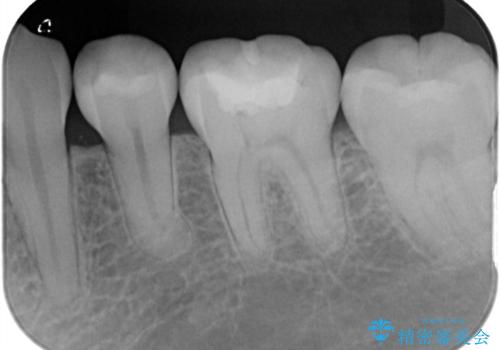

詰め物の下が黒いのが気になる セラミックインレー修復

- 定期健診の際に、他院の詰め物の下が黒くなっているのが気になるとのことで、セラミックインレーで治療し直したケースです。色調も調和しており、術後の経過も良好です。